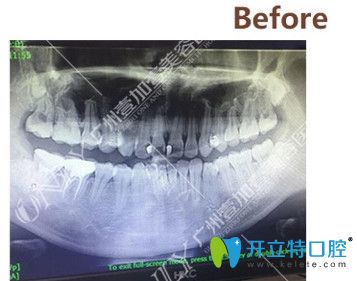

▼矯正前拍攝的CT

矯正前拍攝的CT

拍了CT之后,醫(yī)生根據(jù)我的情況給我進行了分析,我的情況還不算特別復(fù)雜,牙套可以選擇金屬的、半隱形的以及隱形的,問清楚了這幾種牙套的區(qū)別和價格之后,我選擇了價格中等,美觀度稍高的半隱形陶瓷牙套。